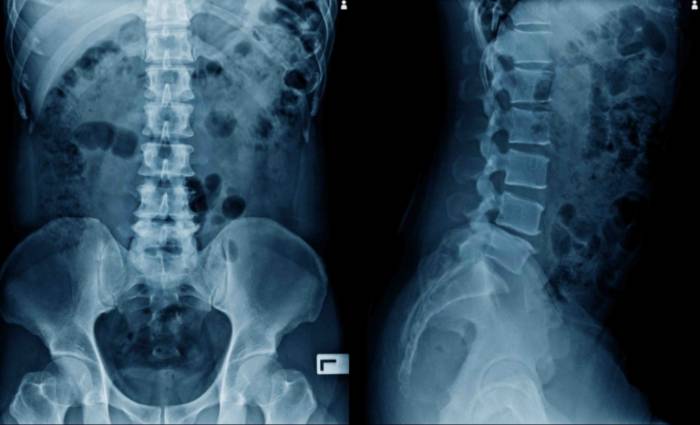

Una hernia es la protrusión de cualquier órgano o tejido fuera del lugar donde se hallan alojados habitualmente. En el caso de la hernia de disco lumbar, se produce cuando un disco intervertebral degenerado se rompe y su contenido se sale de sus límites.

La hernia de disco se produce como resultado de un desgaste natural gradual y relacionado con el envejecimiento llamado degeneración discal. A medida que envejeces, tus discos se vuelven menos flexibles y más propensos a desgarrarse o romperse, incluso con una tensión o torsión menor.